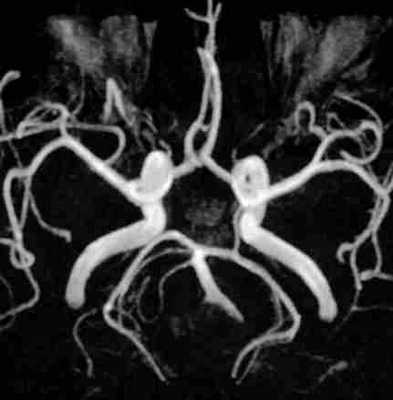

МР-ангиография. Виллизиев круг. Поперечная плоскость.

Атеросклеротические бляшки локализуются, главным образом, в дистальной части внутренних сонных артерий, то есть в шейной её части. Выраженное сужение (более 90%) приводит к уменьшению кровоснабжения мозга (ишемии), либо отрыв материала бляшки вызывает закупорку (эмболию) артерий: глазной, системы среднемозговой, реже - передней артерии мозга. Наибольшая вероятность ишемического инсульта возникает при закупорке (эмболии) сосудов дальше Виллизиева круга, так как они не имеют коллатералей. Атеросклероз может вовлекать и систему базилярной артерии. Здесь поражение чаще идет по типу эмболической окклюзии в бассейне задней артерии мозга. Виллизиев круг (артериальный круг мозга) - это система сосудов в основании мозга, соединяющая систему сонных артерий (передняя часть) и систему базилярной артерии (задняя часть круга). Благодаря соединительным артериям обе системы кровоснабжения мозга объединяются. В случае нарушения кровотока в одной из систем срабатывает переток из другой. Виллизиев круг замкнутый меньше чем у 20% людей. Существует много вариантов его строения, обычно по типу отсутствия (аплазии) или врождённого уменьшенного диаметра (гипоплазии) одной из его составных частей. Такое состояние не рассматривается как заболевание, так как питание мозга не нарушается. Только когда атеросклеротическое поражение крупного сосуда достигает значительной степени, перетоки начинают играть важную роль. Кроме того имеется несколько вариантов редкого строения артерий, питающих мозга. При МР ангиографии это требует понимания, чтобы не спутать с патологией.